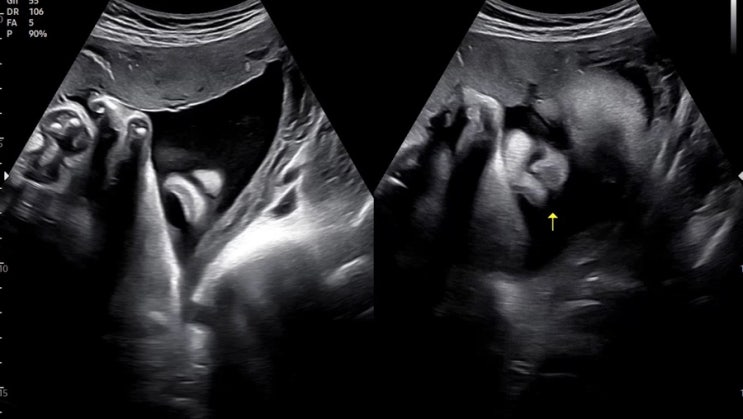

임신일기 34주차 : 정기검진1.8kg, 산전마사지, 만삭사진, 배뭉침, 태동 방광까지 찌릿⚡️

임신일기13 안녕하세요, 오늘도 정기검진을 다녀 온 포스팅과 34주차의 일상얘기를 준비했어요 바로 시작해...